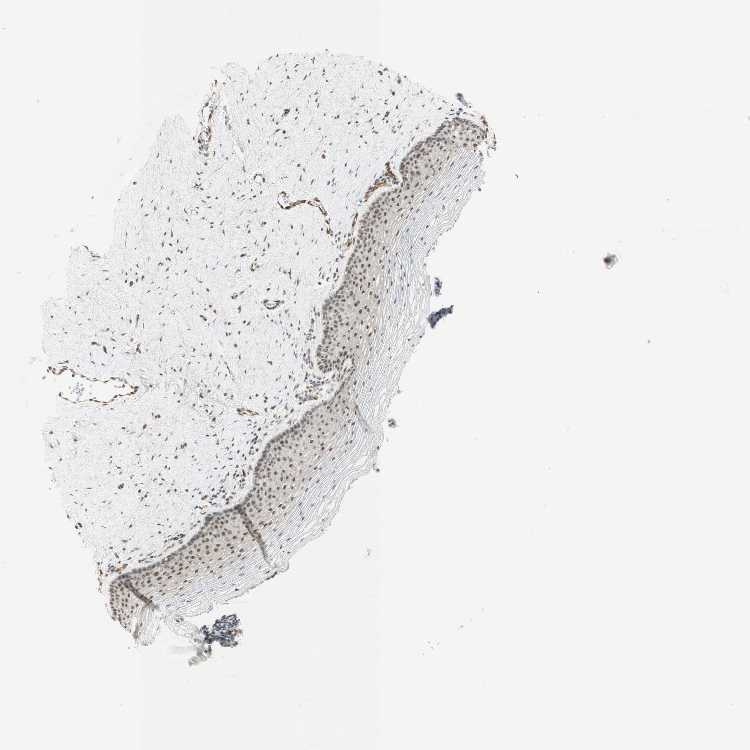

VAGINA - Antibody stainingi

Antibody staining in the annotated cell types in the current human tissue is reported as not detected, low, medium, or high, based on conventional immunohistochemistry profiling in selected tissues. This score is based on the combination of the staining intensity and fraction of stained cells.

Each image is clickable and will lead to virtual microscopy that enables deeper exploration of all samples and also displays staining intensity scores, fraction scores and subcellular localization as well as patient and tissue information for each sample.

Antibody HPA063131Antibody CAB011662

Squamous epithelial cells Not detectedMedium